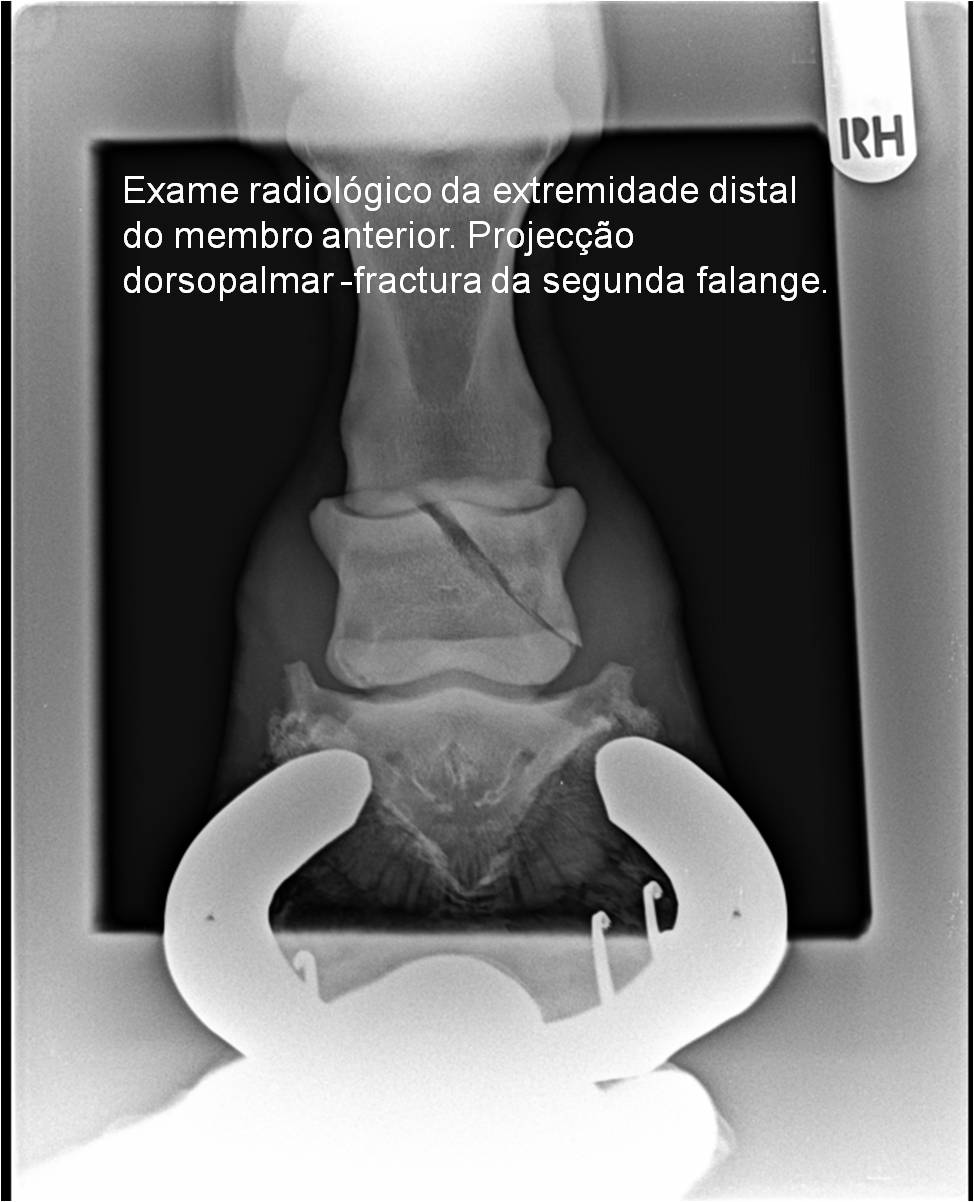

Publisher: Universidade de Évora

Abstract: O relatório de estágio encontra-se estruturado em três partes distintas. A primeira parte faz a caracterização das infraestruturas e funcionamento do Hospital Veterinário de Equinos de Lüsche, Oldenburg, Alemanha, assim como a análise casuística dos casos clínicos acompanhados durante os 6 meses de estágio. A segunda parte consiste de uma revisão bibliográfica sobre quistos do osso subcondral em equinos. Por fim, a terceira parte consta da apresentação e discussão de um caso clínico, nomeadamente o diagnóstico e acompanhamento imagiológico, por ressonância magnética, de um quisto subcondral na terceira falange num cavalo adulto; ### Abstract Equine Practice- Subcondral bone cyst of the third phalanx This internship report is divided in three parts. The first part characterizes the infrastructure and function of the Equine Hospital Lüsche, Oldenburg, Germany, as well as the casuistic of the clinical cases accompanied during the 6 month internship. The second part consists in a bibliographic review of cystic lesions of the subchondral bone in equines. The third part consists in a case report, the diagnostic and imagiological accompaniment, by use of magnetic resonance imaging, of a subchondral bone cyst in the distal phalanx of an adult equine.